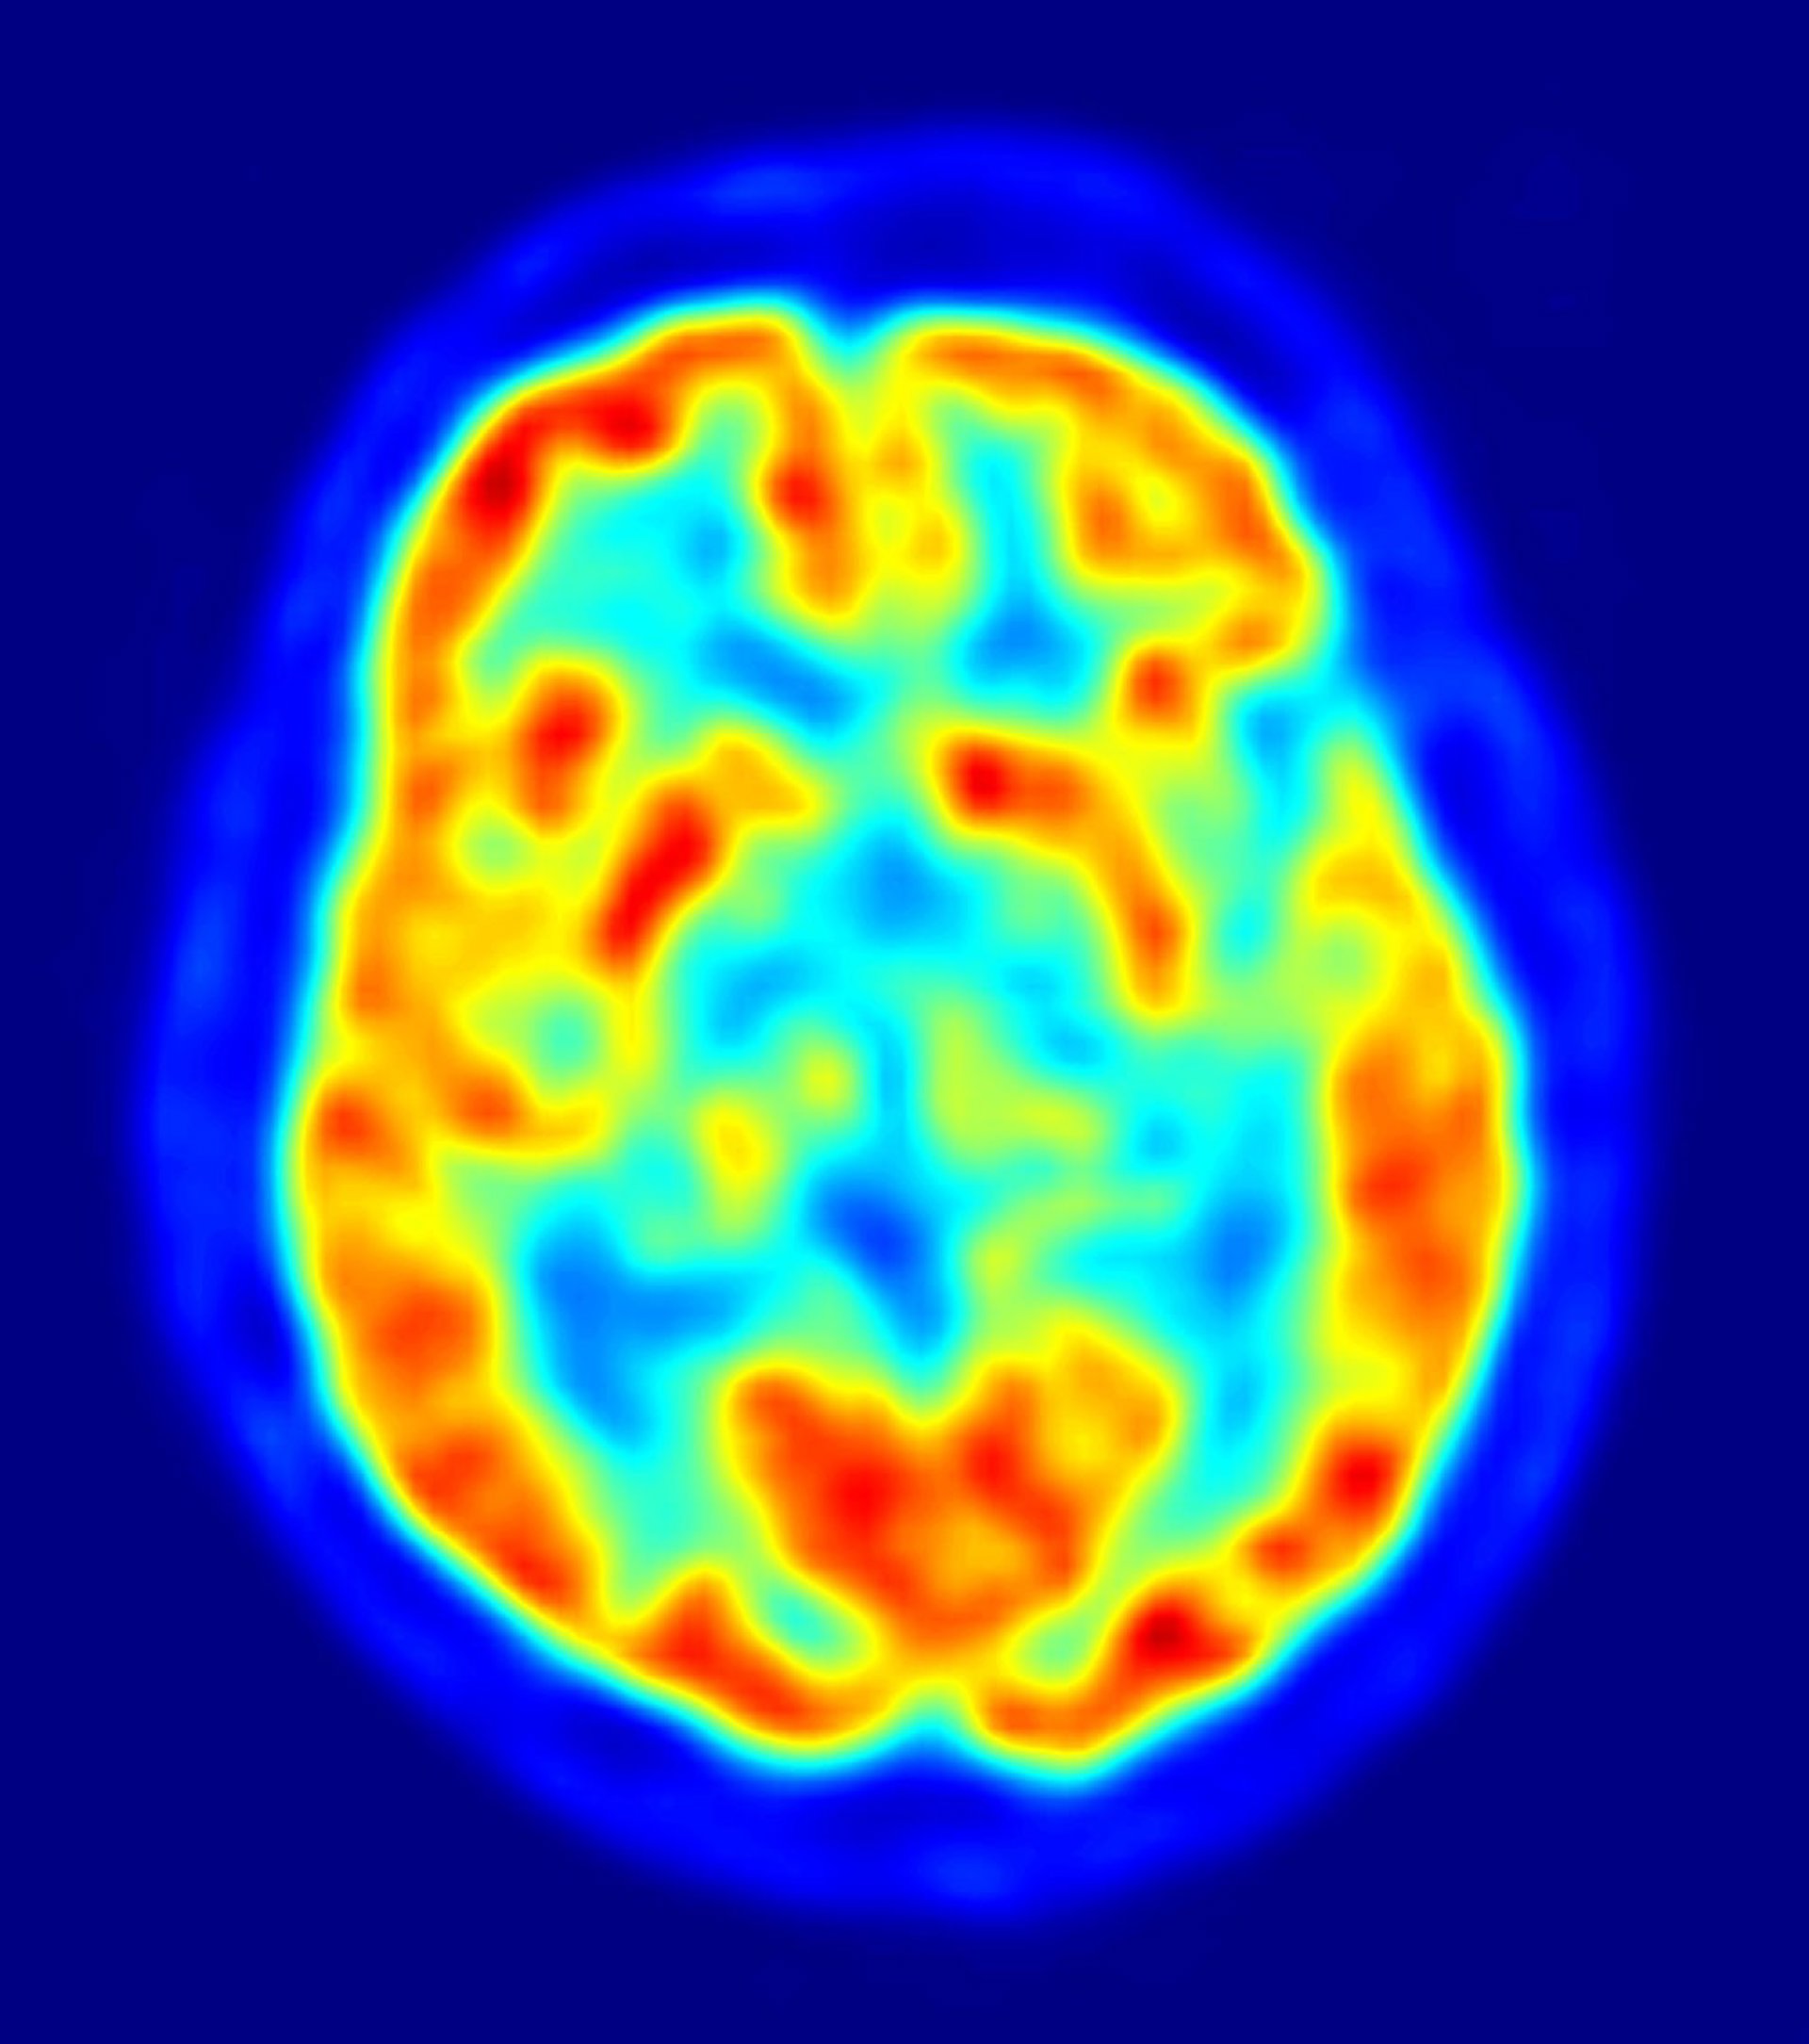

El método de análisis, llamado "clasificación de faro multivariante", divide el cerebro con una malla tridimensional, luego examina cada cubo del cerebro e identifica regiones en las que el patrón de volumen de materia gris podría ser utilizado para discriminar entre los niños con autismo y los niños con un desarrollo típico.

En lugar de comparar los tamaños de las estructuras cerebrales individuales, como han hecho los estudios previos, el nuevo análisis ha generado algo parecido a un mapa topográfico de todo el cerebro. Este tipo de análisis ofrece un enfoque más útil que el anterior. Las estructuras específicas que difieren incluyen la corteza cingulada posterior, la corteza prefrontal medial y el lóbulo temporal medial.

"Podemos distinguir entre niños con un desarrollo normal y niños con autismo con una precisión del 92 por ciento sobre la base del volumen de materia gris en la corteza cingulada posterior", afirma la doctora Lucina Uddin, coautora del estudio y profesora de psiquiatría y ciencias conductuales en la Universidad de Stanford.